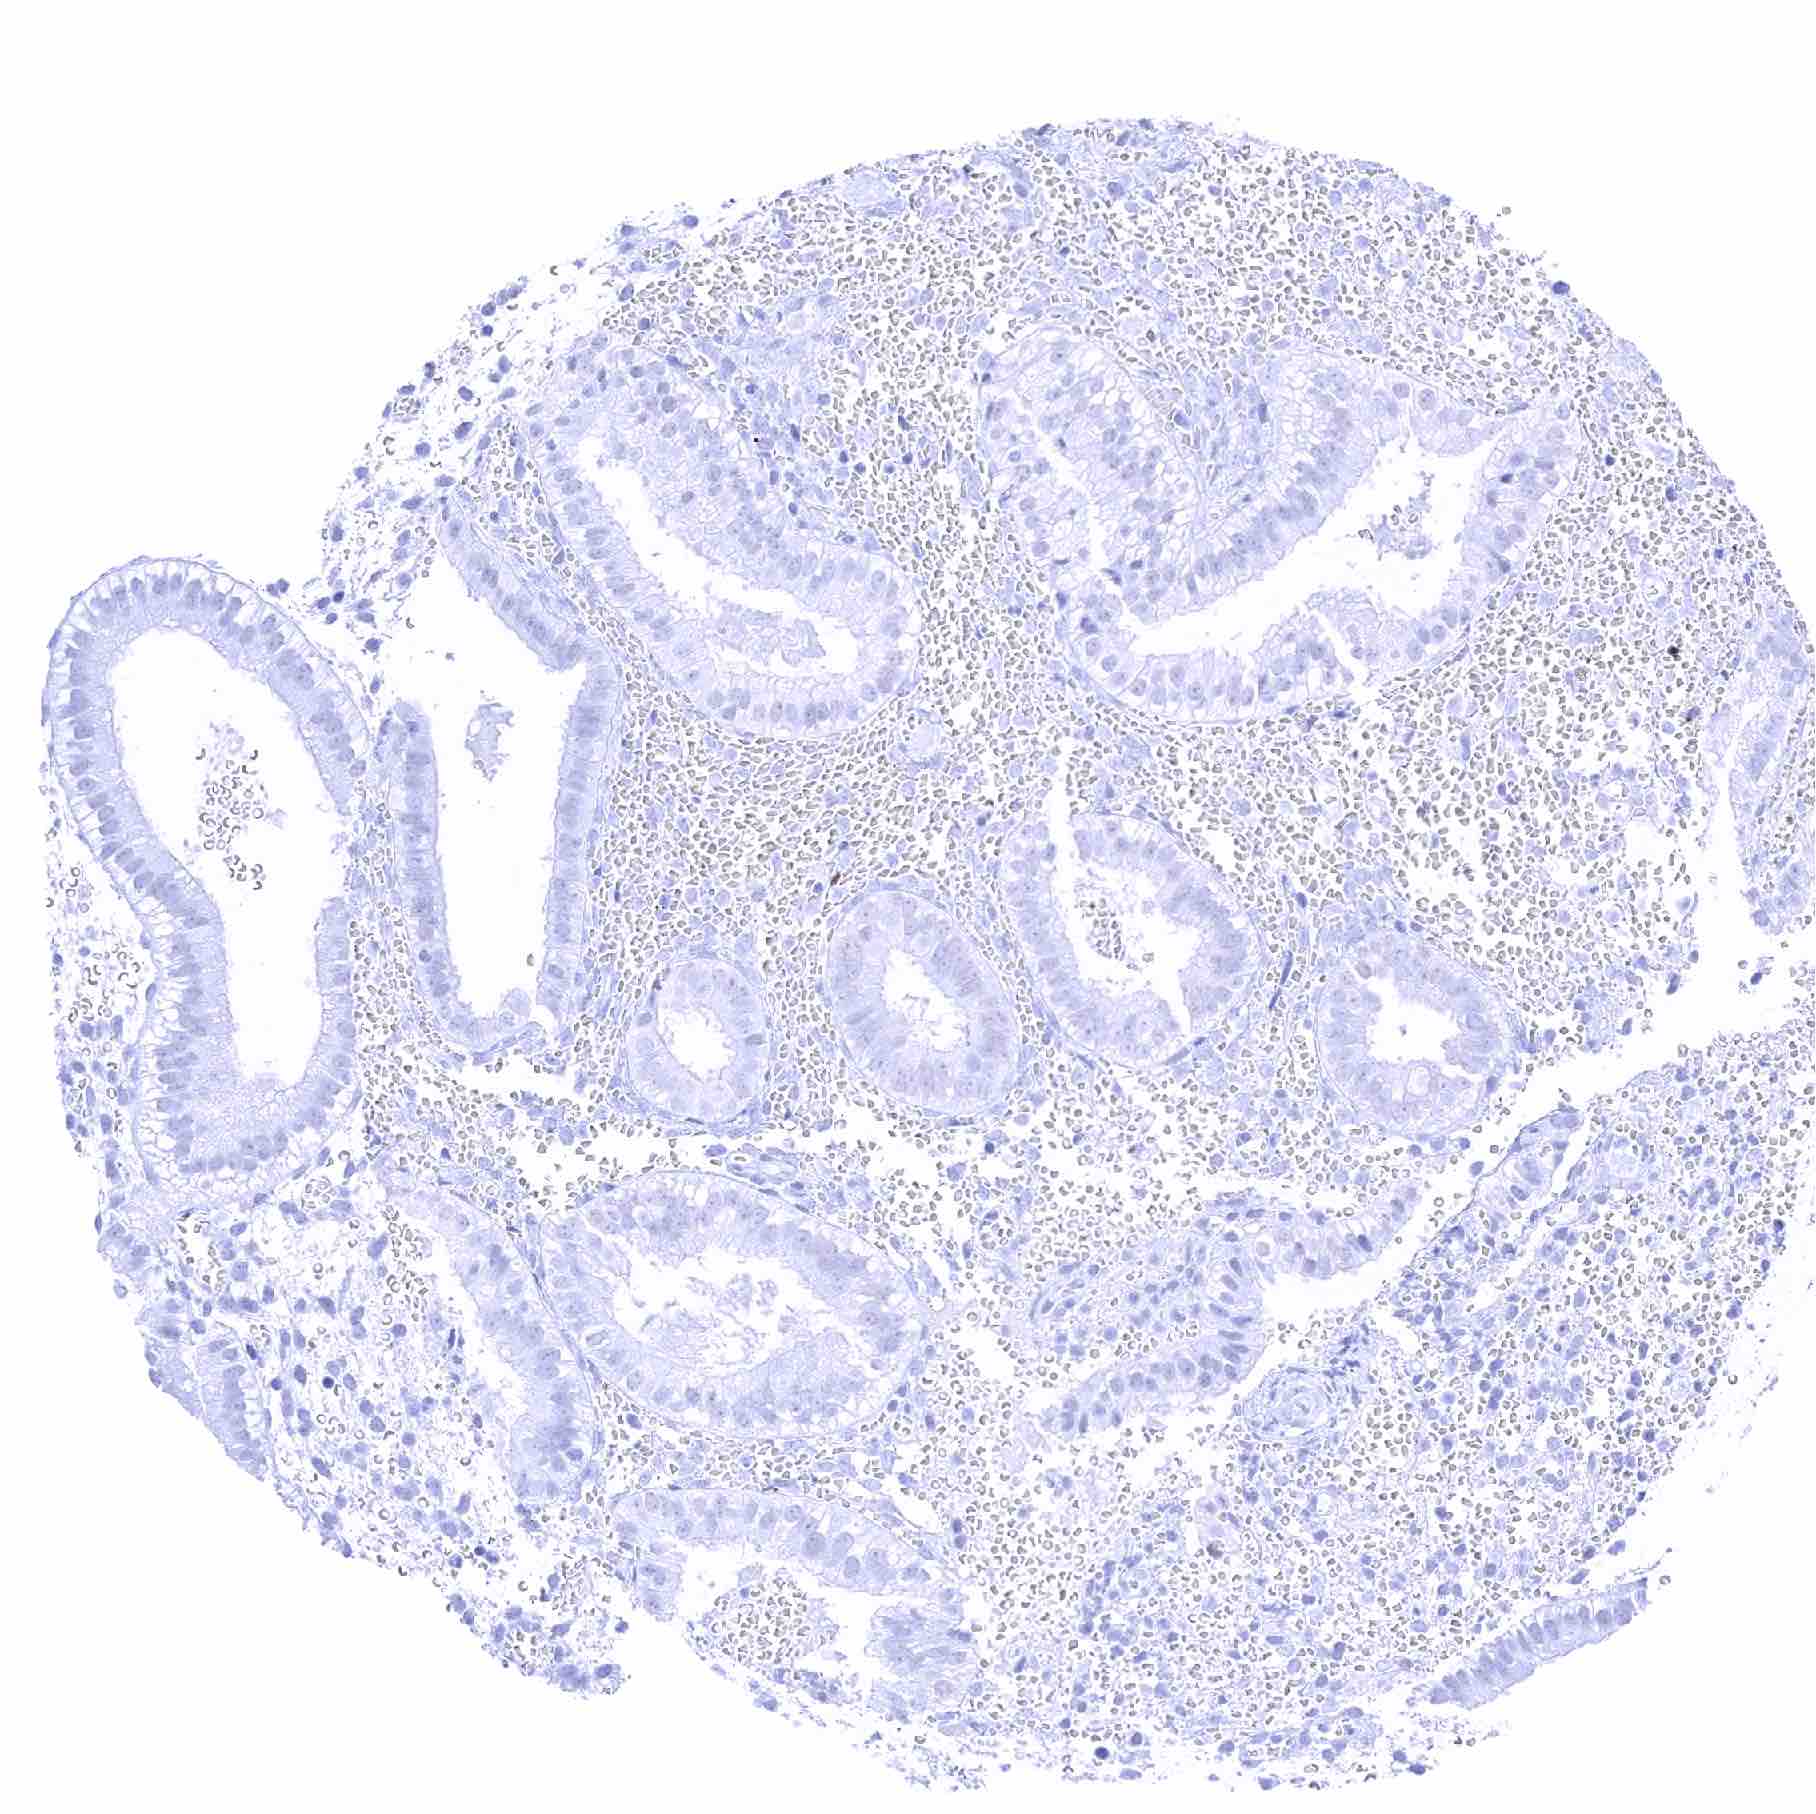

Duodenum, mucosa